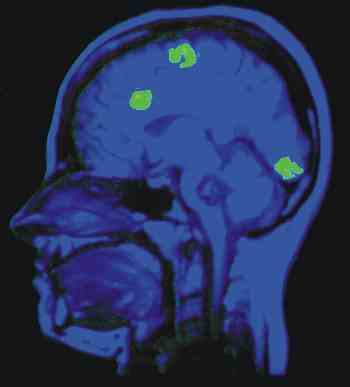

Durch graphische Kombination von morphologischen und funktionellen Daten können wichtige Zusammenhänge veranschaulicht werden. Hier ist diese Kombination anhandt von Messungen der Hirnaktivität dargestellt.

Links sind zwei Bilder überlagert: Ein Kernspintomogramm des Kopfes (blau) und ein Positronenemissions-Tomogramm (PET; grüne Flecken), das erhöhte Gehirnaktivität in drei Bereichen anhandt erhöhter Stoffwechselaktivität darstellt. Die Bilder sind weder gleichzeitig aufgenommen worden, noch stammen sie vom selben Menschen. Die Kernspinaufnahme dient lediglich zur Identifizierung der aktiven Hirnareale. Die räumliche Auflösungen von NMR- und PET-Signalen liegen im Bereich von 1 mm (NMR) bis 7 mm (PET). Beim PET können mit einer besonderen Art von Kontrastmittel (Positronenstrahlern) Stoffwechselwege verfolgt und der lokale Energieverbrauch gemessen werden. Die Registrierung eines Bildes kann einige Sekunden bis Minuten beanspruchen.

Aus: Kandel, E.R., Schwartz, J.H., Jessel, T.M. (1991)